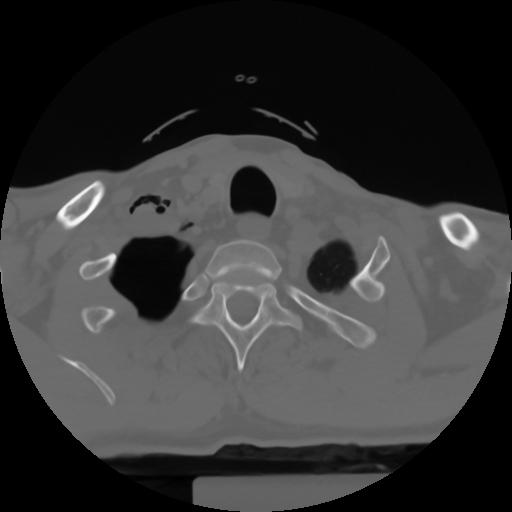

10 P.BLANDAS,,Axial,2.0,P.BLANDAS,,